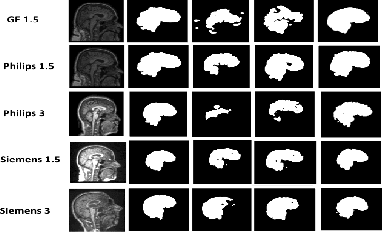

Abstract:Existing domain adaptation (DA) methods often involve pre-training on the source domain and fine-tuning on the target domain. For multi-target domain adaptation, having a dedicated/separate fine-tuned network for each target domain, that retain all the pre-trained model parameters, is prohibitively expensive. To address this limitation, we propose Convolutional Low-Rank Adaptation (ConvLoRA). ConvLoRA freezes pre-trained model weights, adds trainable low-rank decomposition matrices to convolutional layers, and backpropagates the gradient through these matrices thus greatly reducing the number of trainable parameters. To further boost adaptation, we utilize Adaptive Batch Normalization (AdaBN) which computes target-specific running statistics and use it along with ConvLoRA. Our method has fewer trainable parameters and performs better or on-par with large independent fine-tuned networks (with less than 0.9% trainable parameters of the total base model) when tested on the segmentation of Calgary-Campinas dataset containing brain MRI images. Our approach is simple, yet effective and can be applied to any deep learning-based architecture which uses convolutional and batch normalization layers. Code is available at: https://github.com/aleemsidra/ConvLoRA.